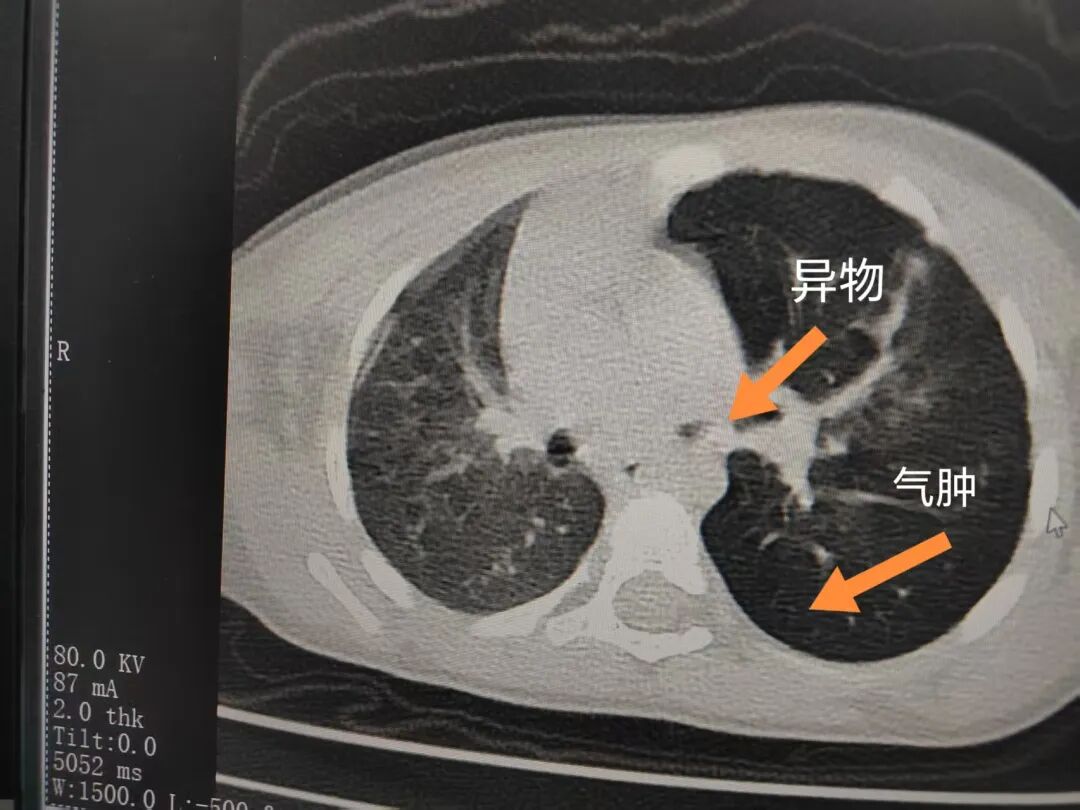

三天后(11月13日),趙寶出現(xiàn)高熱、咳喘加重,家長著急了,再次帶他來到醫(yī)院。CT檢查顯示左肺過度充氣,左肺上下葉支氣管主干見不規(guī)則高密度影,左肺上葉可見大片狀密度增高影,縱隔窗實變,提示為“左側(cè)支氣管內(nèi)異物并繼發(fā)性改變,左肺上葉舌段肺膨脹不全”。

市二院小兒呼吸內(nèi)科團隊迅速為患兒制定了周密的手術(shù)方案,并很快安排了氣管鏡探查。術(shù)中,主治醫(yī)師田慧等憑借嫻熟的氣管鏡操作技術(shù)成功將異物大塊板栗取出。由于板栗在氣管內(nèi)存留時間較長,質(zhì)地軟糯易碎,大大增加了手術(shù)難度。檢查還發(fā)現(xiàn),異物停留部位的氣管黏膜已出現(xiàn)充血紅腫、糜爛,導(dǎo)致患兒住院時間相應(yīng)延長。此次事件給趙寶的家庭帶來了不小的驚嚇與擔(dān)憂,也再次為廣大家長敲響了警鐘。

市二院小兒呼吸內(nèi)科副主任楊亞娟介紹,異物誤入氣道可能導(dǎo)致氣道阻塞,嚴重時可引發(fā)窒息,甚至危及生命。若異物進入支氣管,造成不完全堵塞,可引起阻塞性肺氣腫;如完全堵塞支氣管,則可能導(dǎo)致肺組織萎縮,形成肺不張。此外,若異物存留時間較長,或為植物性異物,容易合并細菌感染,產(chǎn)生膿性分泌物,進而發(fā)展為肺炎。她強調(diào),盡早診斷并取出異物,是減少并發(fā)癥、降低病死率的關(guān)鍵。